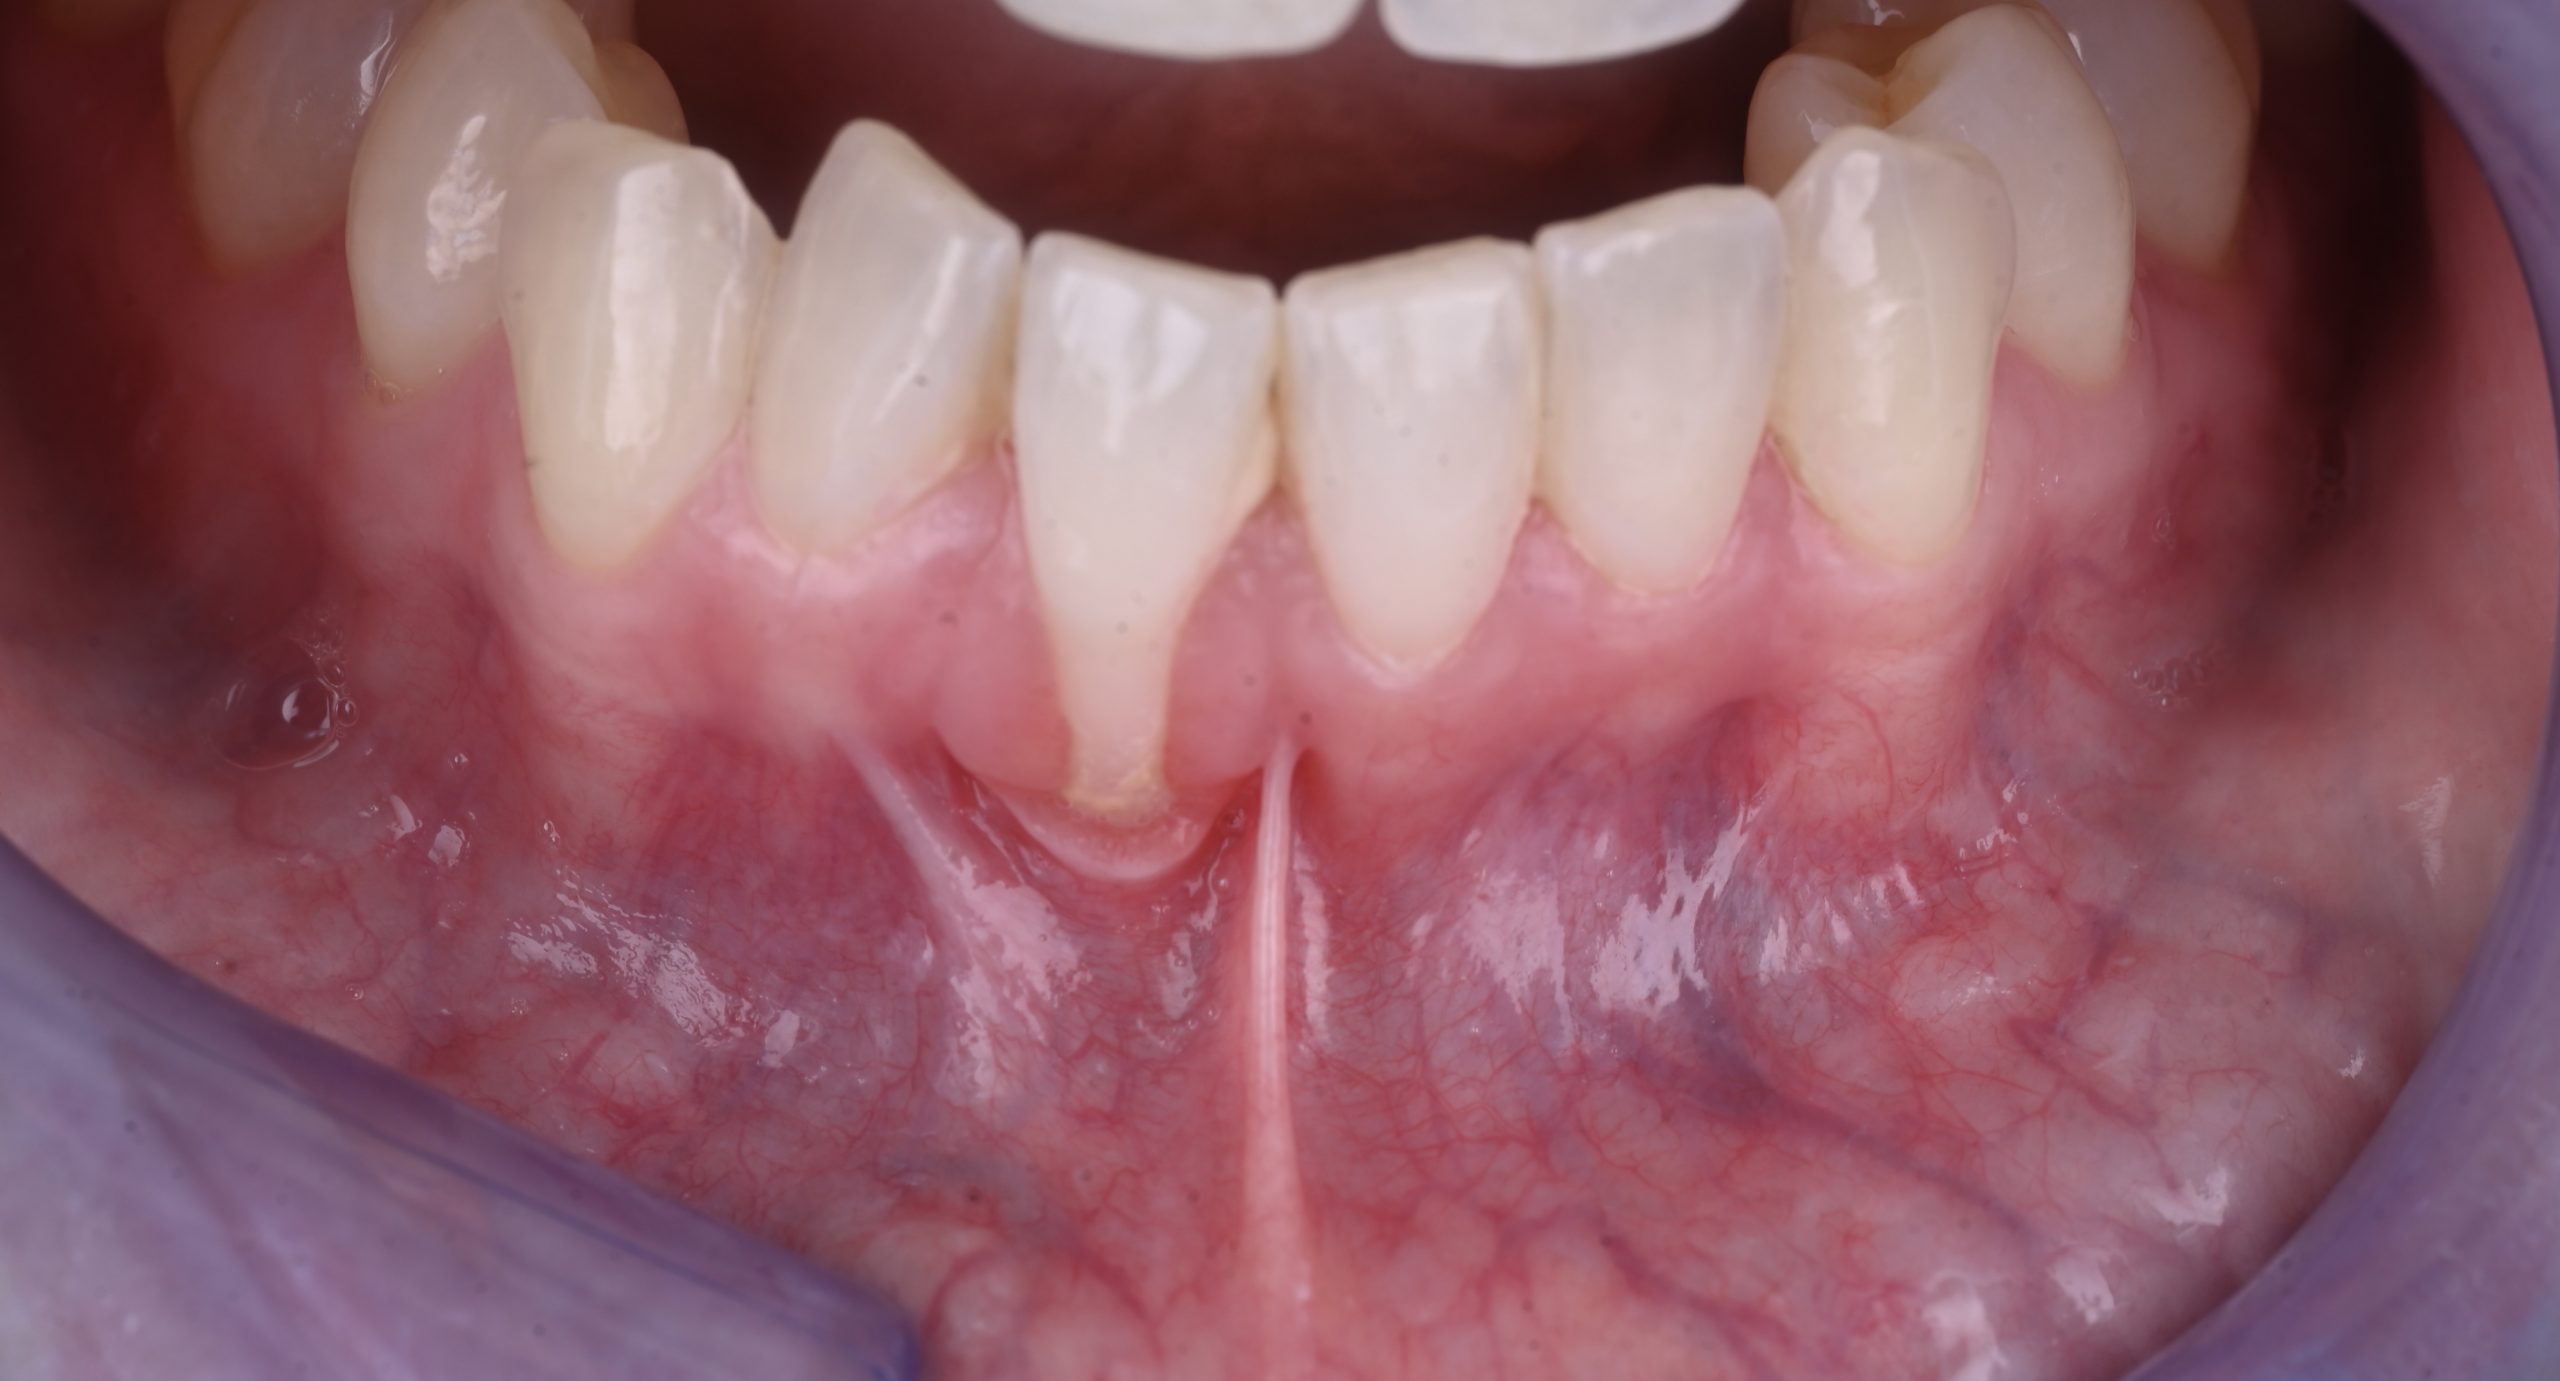

La récession gingivale correspond à un retrait progressif de la gencive qui expose la racine de la dent. Cela peut provoquer :

Une sensibilité accrue au chaud et au froid.

Une gêne esthétique (dents plus longues).

Un risque de caries radiculaires ou de perte d’attache.

Une fragilité osseuse à long terme.